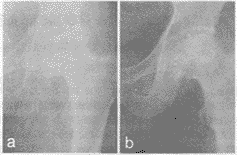

图2 a:创伤致左股骨头无菌性坏死,股骨头轻度扁平,骨质密度增高,股骨头内下方大块骨破损及塌陷; b:术后1个月,股骨头外形经重塑基本恢复正常,大转子下隐约可见开凿的隧道; c:术后3个月,股骨头内骨愈合良好; d:术后2年半,股骨头坏死修复,外形经重塑后变得较为光圆

1. 股骨头缺血性坏死,在彻底清除病灶的基础上植入血运丰富、有修复能力的骨块,无疑是最佳的选择[4]。股骨瓣的移植应遵循就近取材、取骨稍大、血供丰富的原则,应考虑到转移途径方便,血管张力不大,取下骨瓣观察应有滴血现象,取后用温盐水纱布包裹搁置一边,待最后移植时再观察一下血运是否很好再固定(图2a)。本组16个髋应用带股方肌肌骨瓣移植术,股方肌血供为多源性、血管彼此吻合、围绕股方肌形成完整的血管网。另有9个髋采用在大转子处切取带血管蒂的肌骨瓣移植术。从解剖上看,此处股外侧肌群上1/3血供来自旋股外侧动脉的分支、横支和降支,分为1~3组,自上而下与静脉、神经伴行进入肌肉。该肌肉体积大,血供丰富[5]。其供血范围在大转子前、外侧,总体积为3.5cm×2.0cm×3.5cm或3.5cm×2.0cm×4.0cm[6]。此骨瓣植入开窗处不仅有利于股骨头修复,而且能建立一套血运系统。

2. 本组有5例(单髋)因创伤所致的股骨头缺血性坏死的病人。首先,术中在股骨头颈部开窗处沿大转子中轴向骨干另开凿一隧道,此隧道可使股骨颈与大转子下髓腔相通,股骨头可直接接受股骨髓腔血液,加上肌骨瓣的血流就大大改善了股骨头颈的血液供应[7]。其次,在隧道中凿取的松质骨可用来填塞股骨头腔,以弥补髂骨骨量不足。从临床资料看,此5髋与单纯开窗植骨相比,股骨头密度的恢复和负重小梁的重建时间均较后者为早,平均缩短半个月(图2b)。